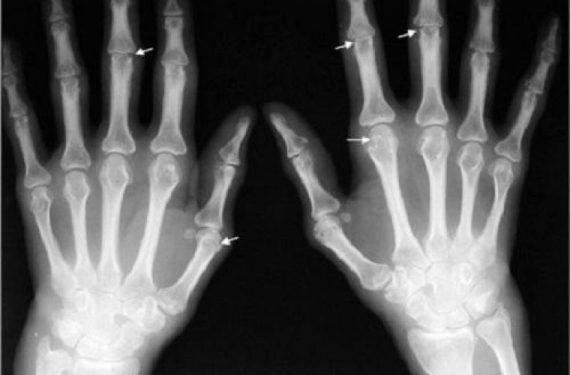

Η ουρική αρθρίτιδα προκαλείται από κρυστάλλους ουρικού οξέος που σχηματίζονται μέσα στις αρθρώσεις. Θα πρέπει επίσης να γνωρίζετε ότι ο κίνδυνος ουρικής αρθρίτιδας ανεβαίνει, όταν η διατροφή σας είναι πλούσια σε πουρίνες.